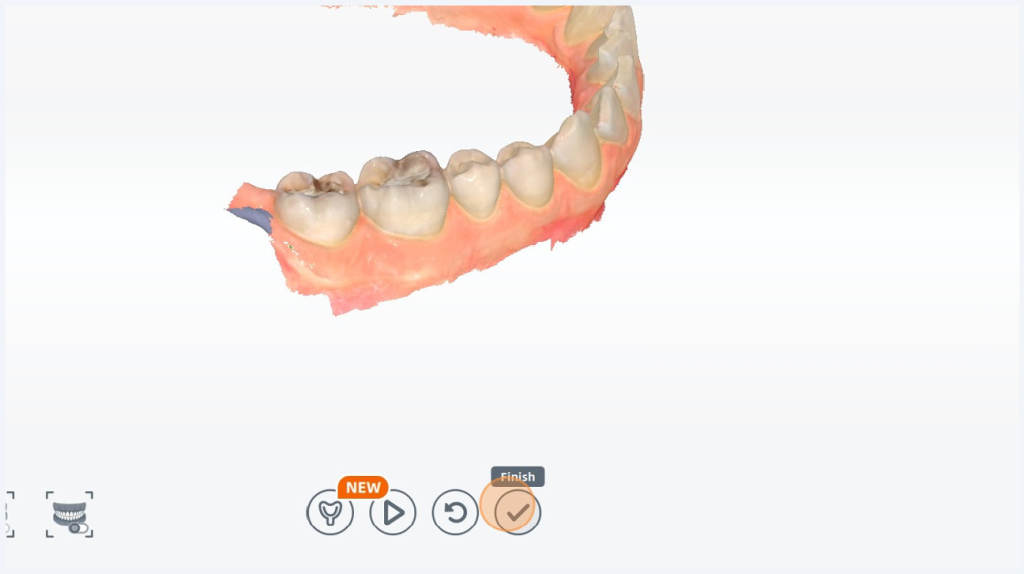

Lower arch is complete. I will now hit the finish check mark.

Now it’s asking for the upper arch. I can hit the play button, or I can click the button on my scanner to start scanning the upper arch. Pause your scan and review it, unpause to fill in any missed data.

Once you are done scanning click Finish